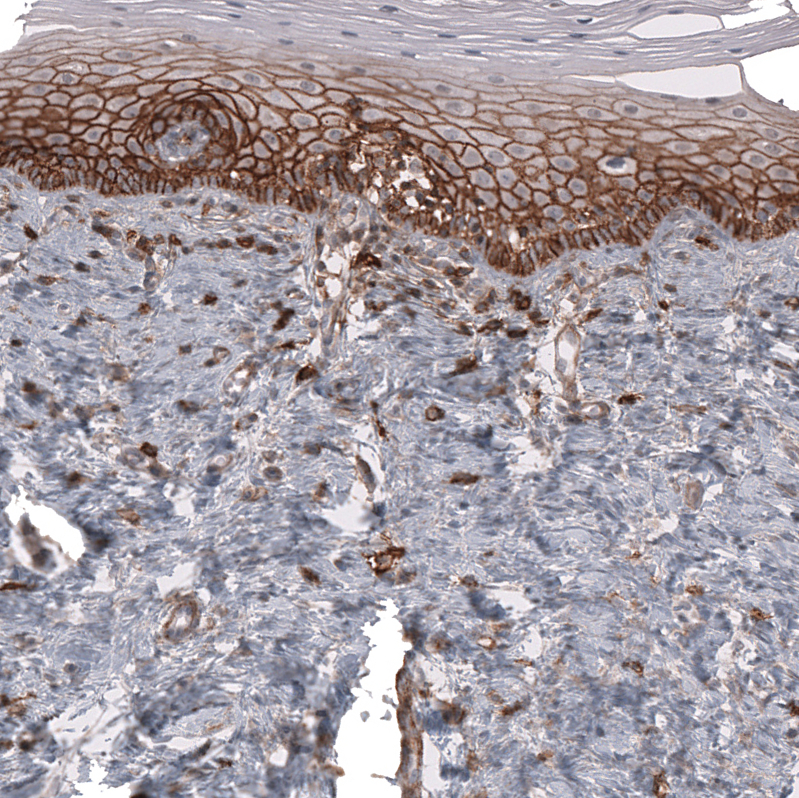

Immunohistochemistry analysis in human cervix, uterine and skeletal muscle tissues using AMAb91845 antibody. Corresponding CD44 RNA-seq data are presented for the same tissues.